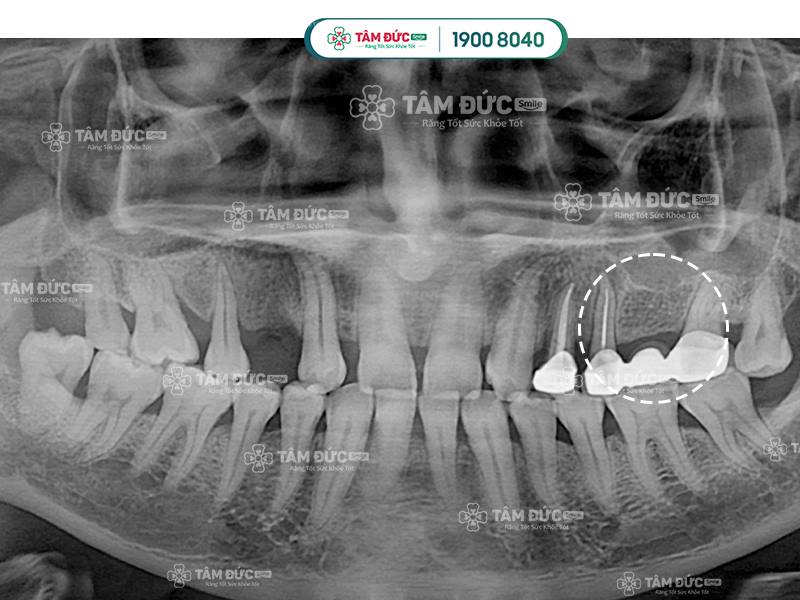

Phương pháp trồng răng Implant ngăn chặn tiêu xương hàm hiệu quả hơn làm cầu răng sứ